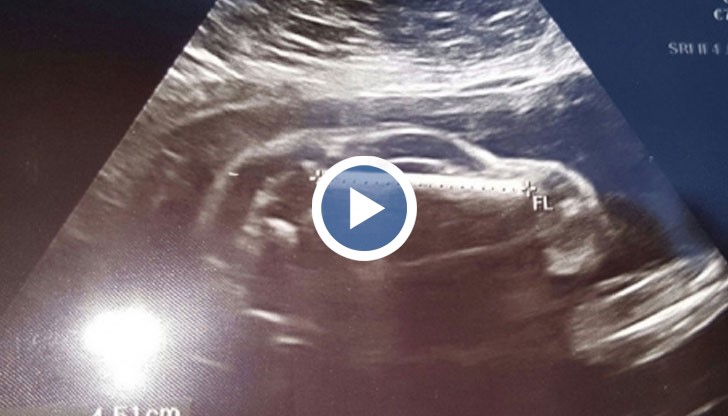

Млада жена в САЩ е "бременна с автомобил".

Тази шега започнал бащата на бебето, след като съпругата му отишла на преглед с ултразвук, сподели Нова телевизия.

Полученият образ напомня силуета на автомобил.

Бащата качил снимка в интернет.

И започнали предположения какъв модел е автомобила. Някои виждат спортни коли. Други - миниванове.

А докторите казали на съпругата на шегаджията, че едно е сигурно - колата е момче и се развива нормално.